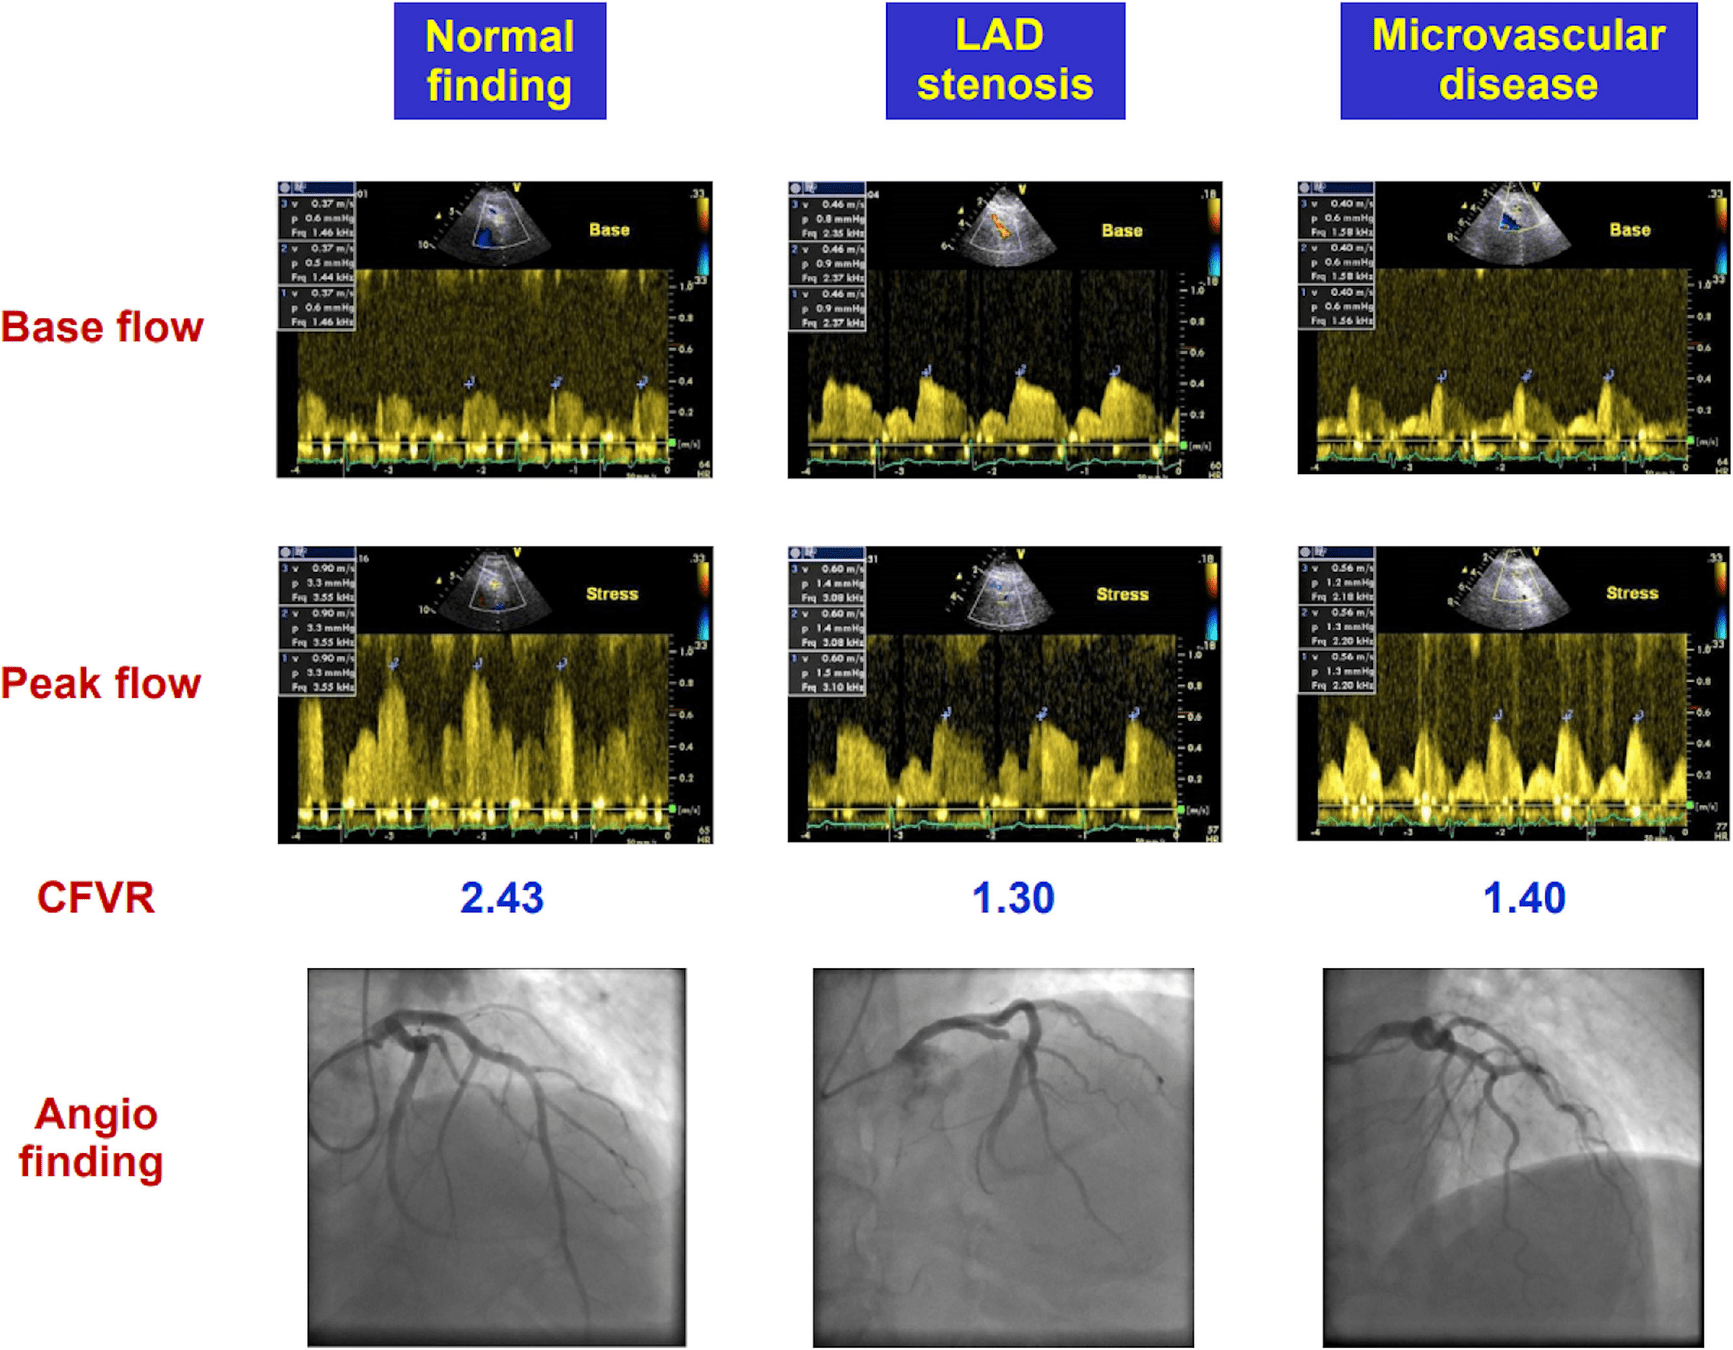

D - Coronary flow reserve

Example: Microvascular Dx